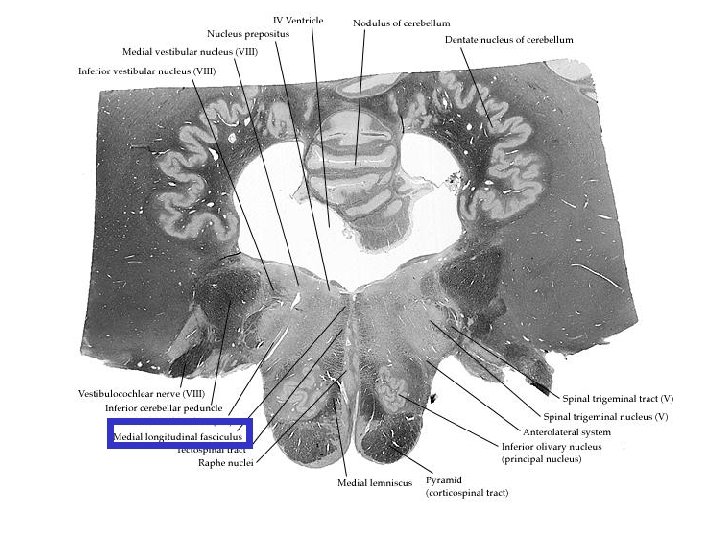

Fasciculus longitudinalis medialis Orta çizgiye çok yakın olarak yer alır. Kafa çiftlerinin birbirleri ile olan bağlantısını sağlar Beyin sapında göz kaslarını inerve eden çekirdekler arasında ve bu çekirdekler ile vestibular sistem arasında önemli rol oynar.